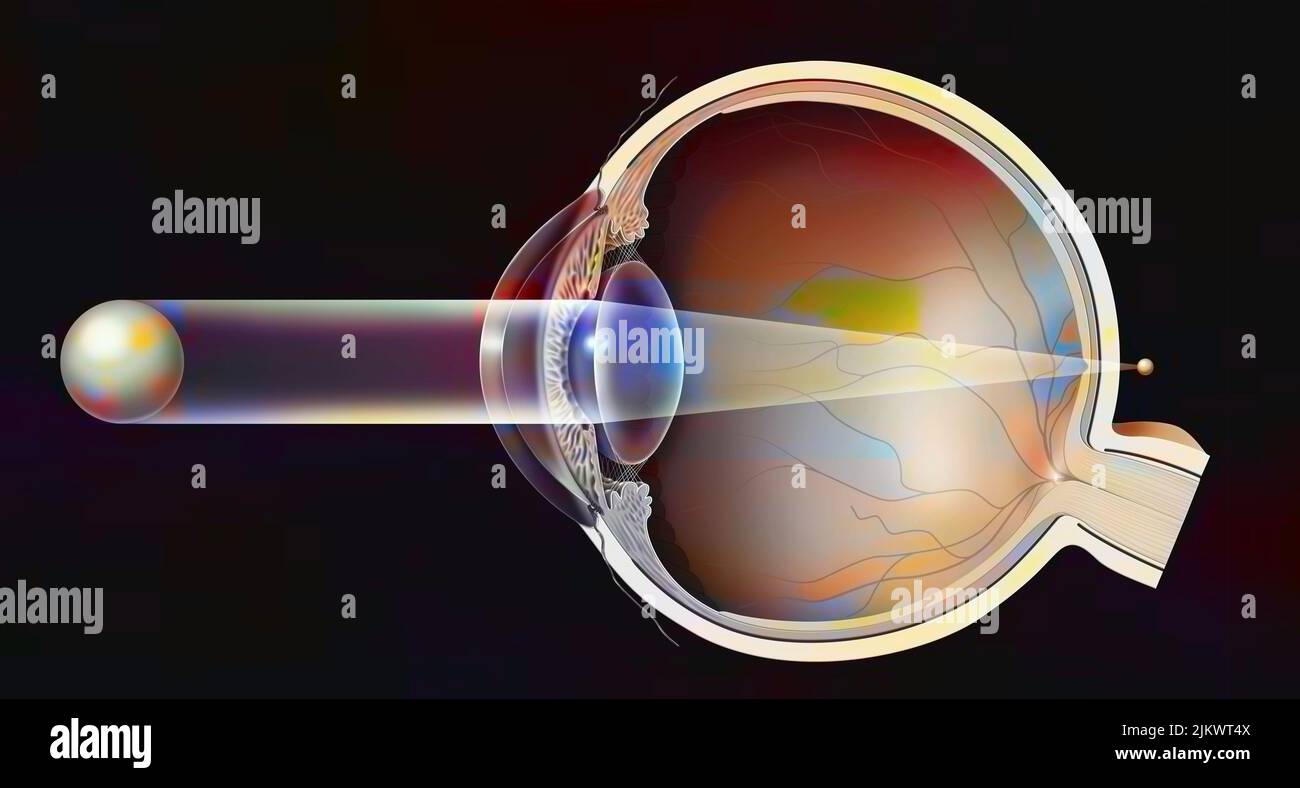

RF2JKWT9A–Oeil, cataracte, phacoémulsification - étape 2: Consiste à casser la lentille avec une sonde.